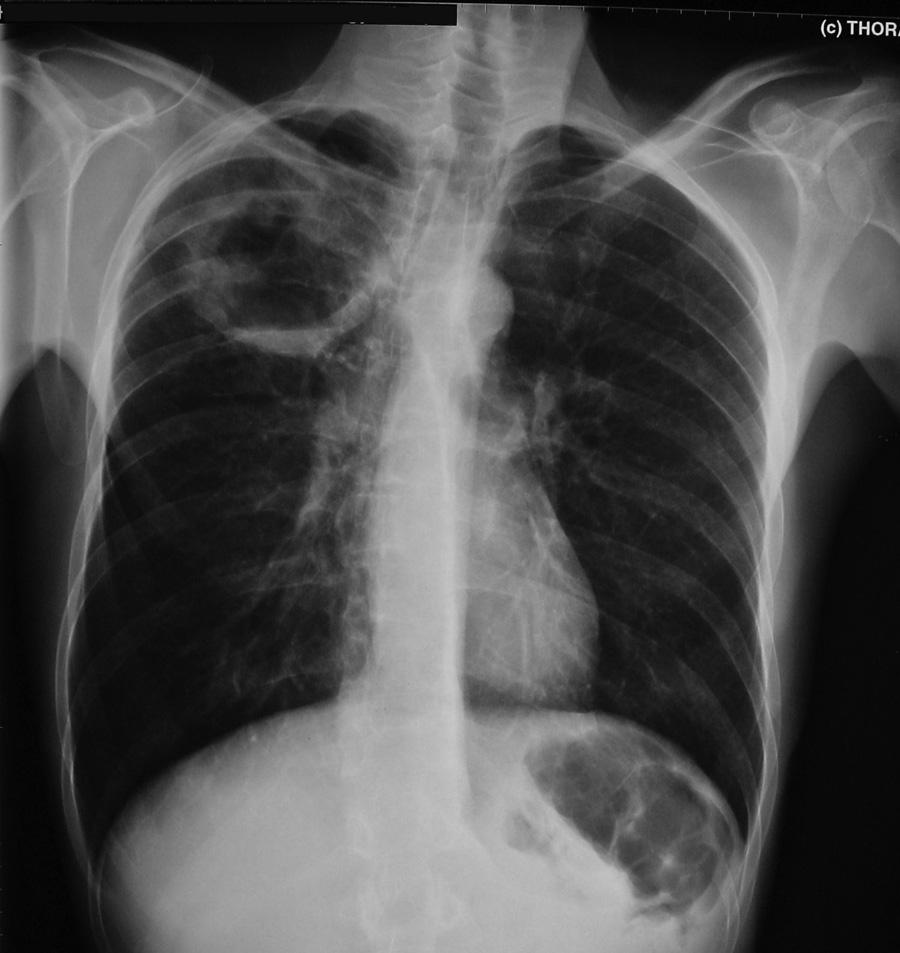

图7 患者男,42岁。发热,痰液恶臭。有大量饮酒史,体格检查发现牙列很差。胸部X线片显示右上叶后段肺脓肿

图8 一名患者的胸片,有难闻异味、痰苦,厌氧菌肺脓肿的特征性诊断

在胸部X线片上,肺脓肿表现为孤立的空洞,具有气液平面。周围斑块状浸润有助于区分肺脓肿与空洞性肺癌。

在胸部X线片,发现脓胸而不是肺脓肿的气液平面向胸壁延伸,气液平面跨过肺裂延伸,并逐渐变细。

下图为成年患者的肺脓肿

图9 患者男,42岁,发热并痰液恶臭。有大量饮酒史,体格检查牙列很差。胸部X线片显示右上叶后段肺脓肿。CT扫描显示一个薄壁空洞,周围有实变。